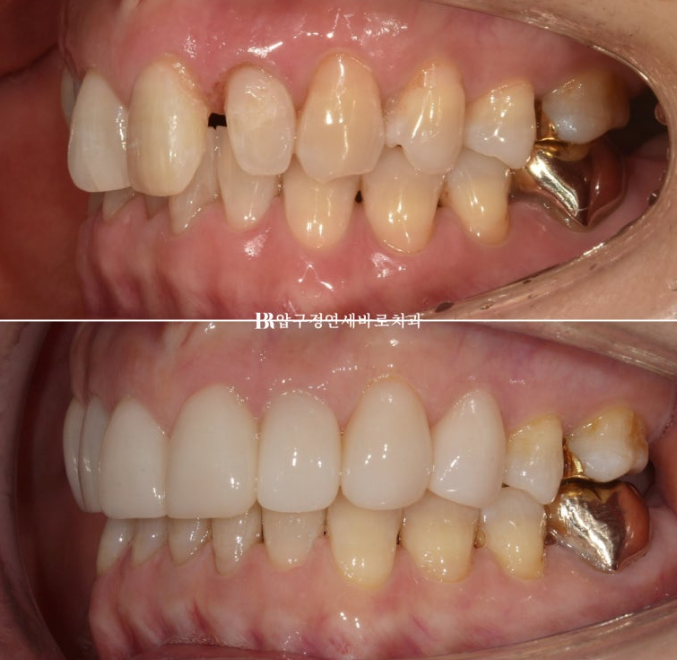

Here is a comparison of the before-treatment and after-treatment photos, including Gelami.

23.09~24.08

Who would think this patient is in their 50s?

The teeth and smile look like they’re in their 20s, right?